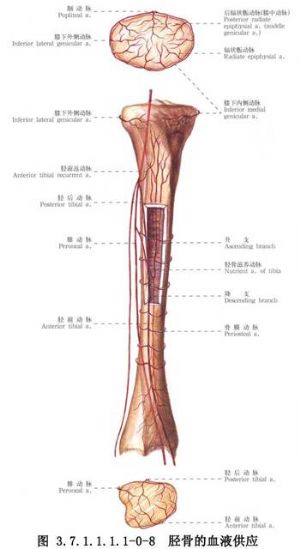

脛骨幹骨折不癒合有多種手術治療方法,需要根據骨折不癒合的類型、骨折對位對線及軟組織情況予以選擇。但要注意儘量選用方法較簡單,創傷小和局部血循環破壞少的手術。脛骨幹骨折影像表現及解剖見下圖(圖3.7.1.1.1.1-0-5~3.7.1.1.1.1-0-8)。